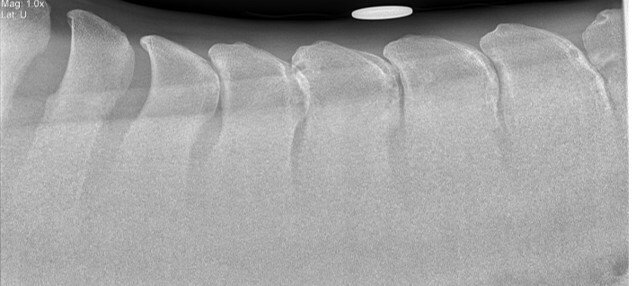

What disease is this?

A

Dorsal spinous process impingement/’kissing spines’ in mid thoracic region with bony remodelling (halos of sclerosis)